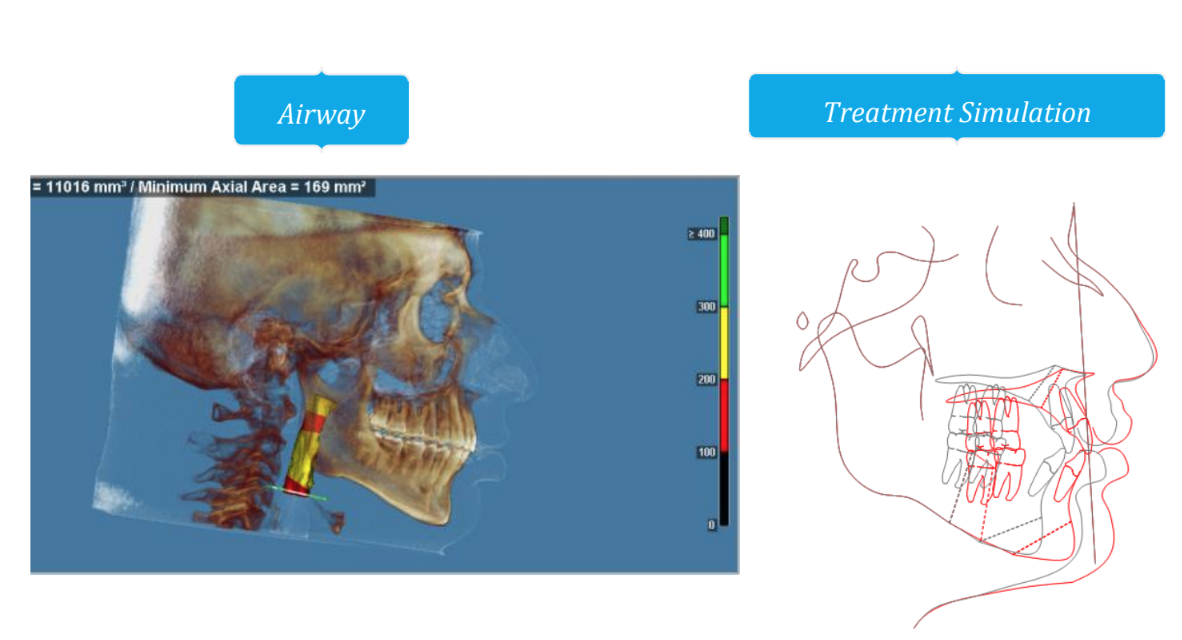

Going with LACOMS in June, probably the best bimax surgeons ITW after Dr. Kasey Li. I don't want to skimp and I am willing to pay extra because I have crippling sleep apnea which totally fucked up life for me.

They are planning on doing a segmental 3-piece Lefort 1 which should give me about 5mm of expansion and 8mm of advancement, along with a CCW rotation of a few degrees (my dumbass forgot to ask how many) and a BSSO mandibular advancement of 12mm.

Feel free to ask any questions, also if any autists out there want to make comments about my scans, current appearance and my surgery plans then please do so.